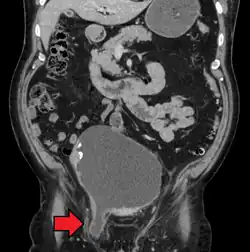

An inguinal hernia which contains part of the bladder. Bladder cancer is also present.